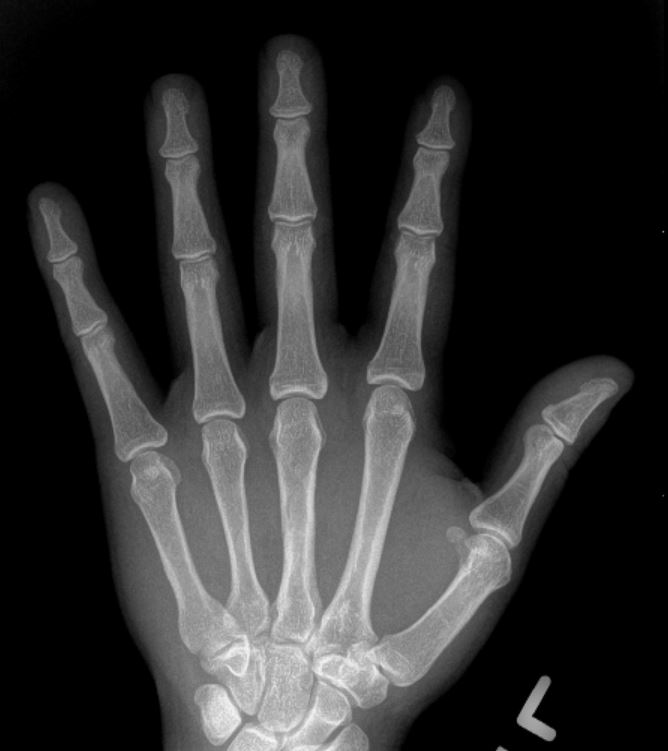

Doctors use medical history, physical examination, X-rays, and lab tests.

RA is diagnosed through symptom review, physical exams, X-rays, and lab tests. Early diagnosis—within 6 months—is important to slow or stop disease progression. Treatments focus on reducing inflammation and preventing joint damage.